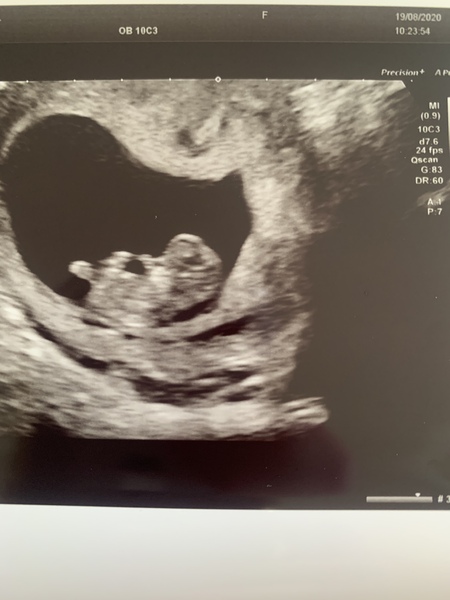

So all good at my scan 😁😍 measuring around 9w6d so got to go back in 2.5 weeks for my 12 week scan and they will officially date baby then. But lovely strong heartbeat and 2arms and 2 legs waving about on the scan 🤩